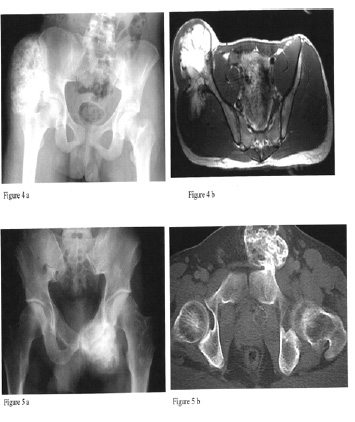

Pelvic Girdle (Hips and Pelvis) |

Osteochondromas of the proximal femur (Figure 3) may lead to progressive hip dysplasia. There have been reported cases of acetabular dysplasia with subluxation of the hip in patients with MHE. This results from exostoses located within or about the acetabulum that may interfere with normal articulation.

Pelvic lesions (Figures 4 and 5) may be found on both the inner as well as outer aspect of the pelvic blades. Large lesions may cause signs of compression, both vascular and neurological. There have also been reports of exostoses interfering with normal pregnancy and leading to a higher rate of Cesarean sections. To view more x-rays please view the MHE Research Foundations image galery

Diagnostic Procedures: Manual palpation is sometimes very difficult in these deep lesions. The orthopedist will check range of motion (“ROM”) by manipulating (moving) the leg in different directions. The orthopedist will also check measurements on each leg to see if there is a difference in limb lengths. X-rays or other imaging tests may be ordered.